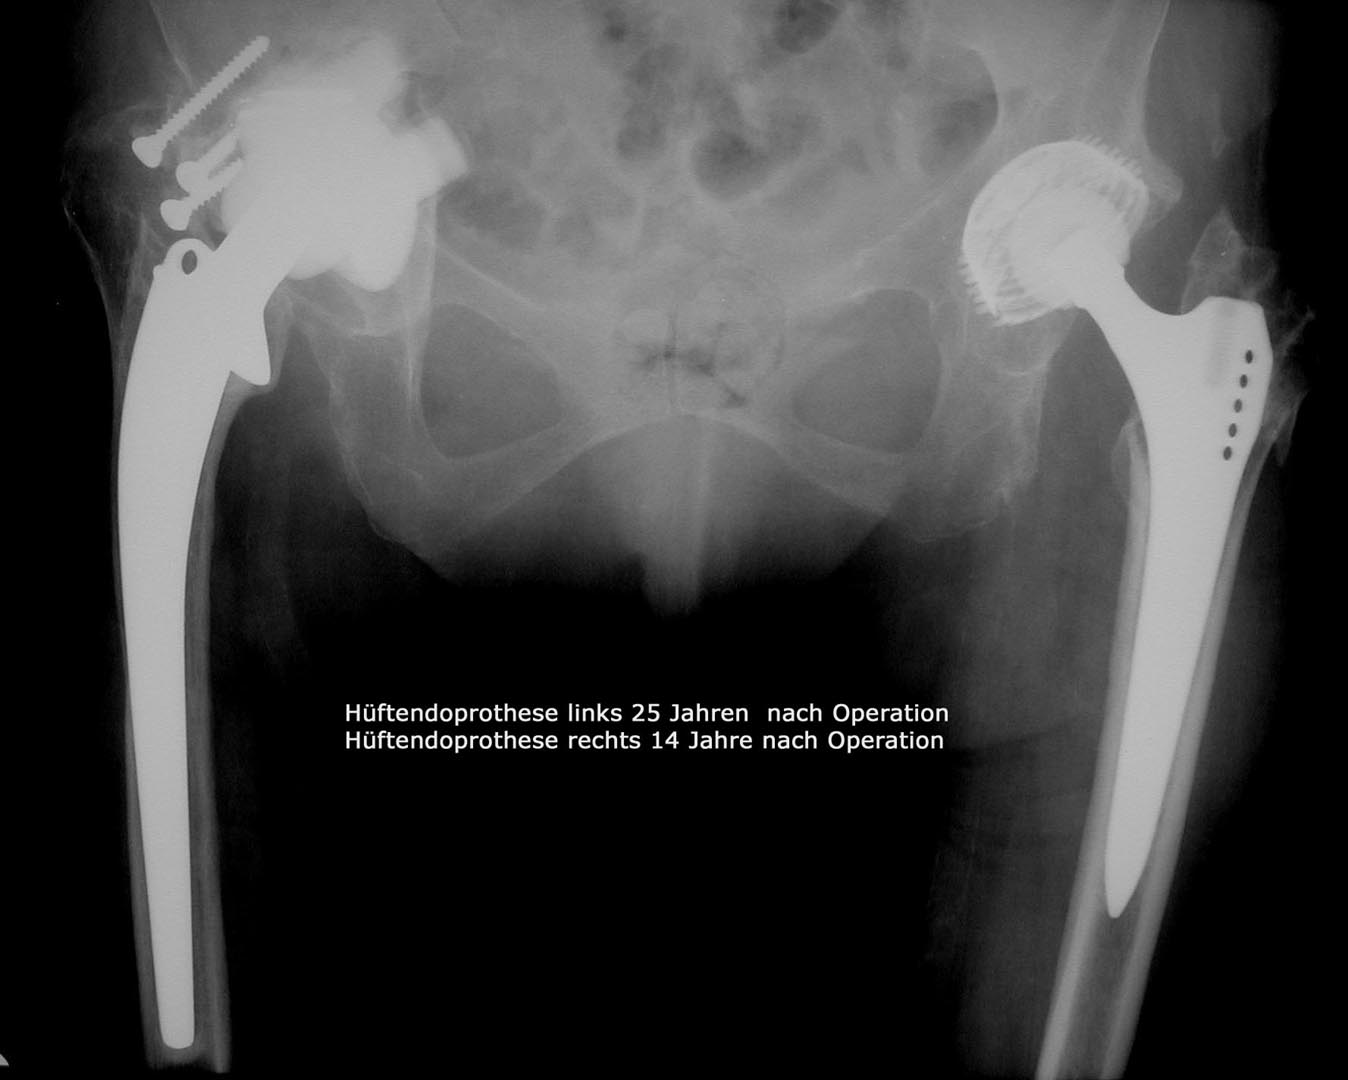

Hüftprothese

Die Hüftoperation bei Abnützungserkrankungen des Hüftgelenks wird in der übergrossen Anzahl der Fälle mit sogenannten zementfreien Prothesen durchgeführt , was bedeutet , dass die beiden Prothesenteile, also Pfanne und Schaft direkt in  Hüft und Oberschenkelknochen verankert werden können.

Dies ist zum einen durch passgenaue Fräsvorgänge der Knochen und zum anderen durch besondere Merkmale der Prothesenform selbst und der Oberflächen der Prothesen möglich. In Kombination mit der Keramik/Keramik Eigenpaarung , die für eine grosse Verschleißfestigkeit schon über Jahrzehnte bekannt ist ( siehe eigene Publikationen – Wissenschaftliche Tätigkeit) ist damit eine dauerhafte,stabile Verankerung und eine gute Funtion gewährleistet.